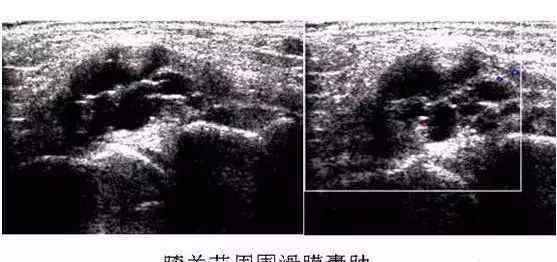

半月板纵向纵裂距离2mm,水平撕裂距离3 ~ 4mm,径向垂直撕裂距离5mm以上,超声可显示。纵向纵裂容易超声显示,但半月板内缘撕脱难超声显示。弯月面完全破裂时,间隙较宽,可看到两个强回声界面,其间有一个低回声声迹近似“=”。见下图。

小的不完全分离的撕裂伤,大多呈线性强回声。当半月板退化时,其特征是半月板内部回声不均匀,表面不完整和钙化。半月板水平撕裂在超声上很难显示,当撕裂较大时,半月板出现水平低回声区。当半月板撕裂发生时,尤其是边缘撕裂时,可能会发生囊变,导致半月板囊肿。超声显示半月板区或基底部分出现液体暗区,并向外突出。见下图。